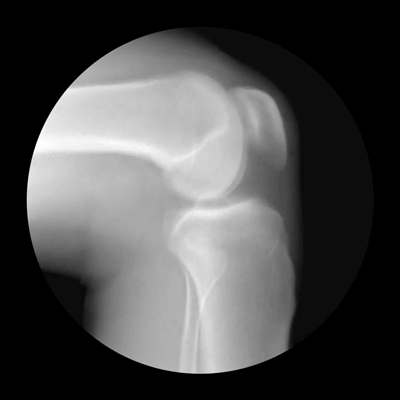

Οι παρακάτω φωτογραφίες, για την ακρίβεια πρόκειται για ακτινογραφίες του ορθοπεδικού Noah Weiss ο οποίος σε συνεργασία με τον φωτογράφο Cameron Drake, δημιούργησαν αυτές τις εκπληκτικές απεικονίσεις. Με τον τρόπο τους, ρίχνουν φως στο τι συμβαίνει στις αρθρώσεις.